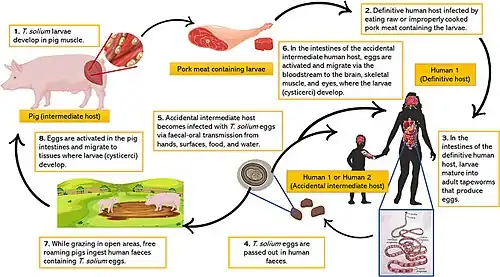

Taenia solium, otherwise known as “the pork tapeworm”, is a tapeworm in the Cestoda class and is a species of the genus Taenia.[22] Taenia solium is a unique tapeworm because it can infect humans in two ways: as a definitive host (where the adult worm lives in the intestines, known as taeniasis) and as an intermediate host (where the larvae develop in tissues, known as cysticercosis).[23][24]

The normal life cycle of Taenia solium involves humans as the definitive host and pigs as the intermediate host. The adult worm lives in the human small intestine and can grow up to 10 meters, though most reach 2–3 meters. Its head (scolex) is small (about 1 mm), round, and has 22–32 hooks arranged in two rows. Since pigs eat feces, the eggs remain in waste, increasing the chance of transmission.[25]

In geographical areas where Taenia solium is common, poor sanitation and free-roaming pigs make it easy for pigs to consume human feces or contaminated food scraps. Once a tapeworm egg enters a pig’s intestine, it hatches into a larva called an oncosphere. This larva penetrates the intestinal wall, enters the bloodstream, and travels through the body until it settles in a tissue site. There, it develops into a cysticercus—a fluid-filled sac containing an immature tapeworm head (protoscolex). When a human eats undercooked infected pork, the protoscolex attaches to the intestine and matures into an adult worm.[26]

The life cycle of Taenia solium is completed when humans eat raw or undercooked pork containing mature cysticerci. However, humans more commonly become infected by ingesting tapeworm eggs through contaminated food or water.[26] When Taenia solium larvae is ingested, the larvae hatches in the insetines and the oncospheres penetrate the intestinal mucosa before migrating to other parts of the body such as the CNS where they develop into vesicular (viable) cysticerci.[27] Since Taenia solium proglottids are not motile and may break apart before being passed, infected feces can contain a high concentration of eggs. Contact with such feces can lead to infection with multiple cysticerci. These cysts take about three months to mature, and their effects depend on their number and location in the body.[26]